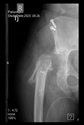

Figure 3.

The 3D-printed hemipelvis with the aiming device in the OR.